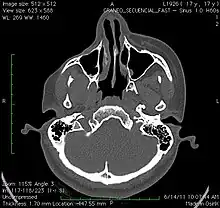

A CT image of the head of a 17-year-old girl with Parry–Romberg syndrome, showing atrophy of the subcutaneous tissue and underlying muscle, with no apparent involvement of the bone structure.

An axial CT scan of a 17-year-old girl with Parry–Romberg syndrome, showing severe loss of subcutaneous tissue and muscle of the right side of the face, with no apparent involvement of the facial bones